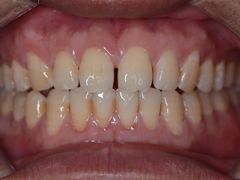

• 新达口腔(华东理工大学店)

• -新达口腔(华东理工大学店)